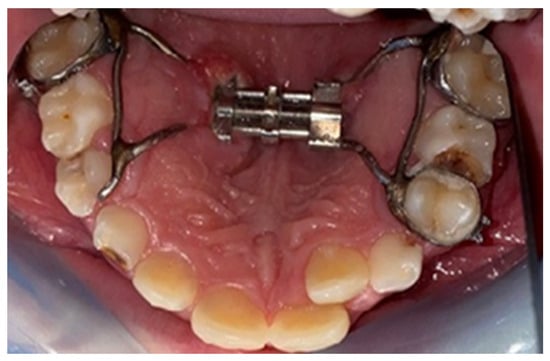

2.2. Palatal Expander Placement

2.3. Assessment of the Study Group